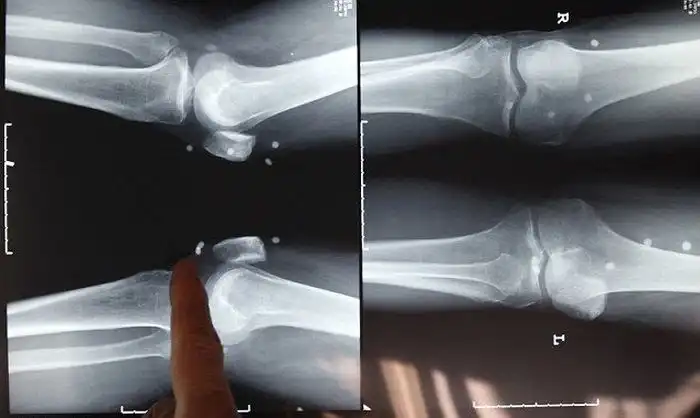

В Китае к народному знахарю пришёл мужчина, который жаловался на боль в спине. Китайский "врач" прибегнул к нетрадиционному способу лечения - зашил дедуле под кожу 42 жемчужины. Сначала 61-летний пациент почувствовал себя лучше, но чуть позже ему стало сложно передвигаться. Спустя некоторое время, старичок решил вновь обратиться к этому лекарю, но уже не смог его обнаружить, потому что тот переехал. Пришлось идти к традиционным врачам, которые были шокированы вшитыми под кожу жемчужинами. Как говорят врачи, жемчужины нанесли костям серьезный урон. Теперь мужчине предстоит, как минимум, операция по протезированию тазобедренного сустава.